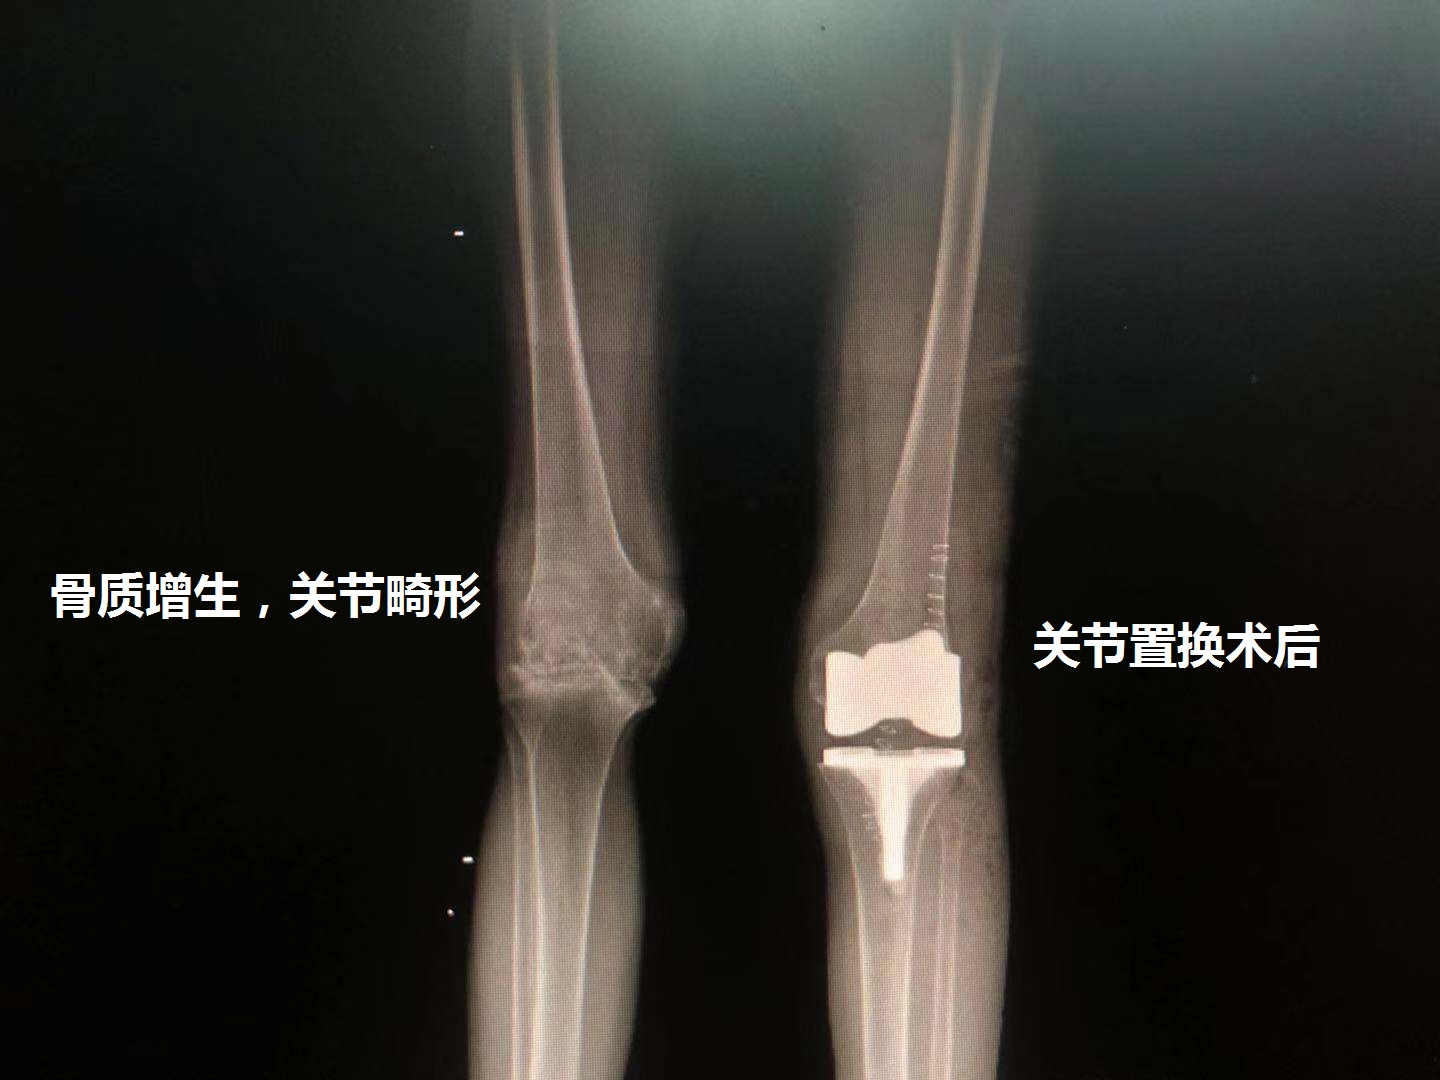

关节畸形:骨质增生、关节炎明显,膝关节已经出现明显的畸形。关节内的无菌性炎症因子会腐蚀关节内的组织,导致膝关节出现严重畸形,对于膝关节患者来说,膝盖没法弯曲跟伸直,关节活动度非常的差,对于这种病人来说,保守治疗已经基本没效果,再尝试保守治疗也可能于事无补!

总结:膝关节炎导致的骨质增生早期可以采用保守治疗为主,到后期关节活动受限、关节疼痛明显则考虑手术治疗,而手术不是单纯的去除骨质增生治疗,而是选择关节置换手术。